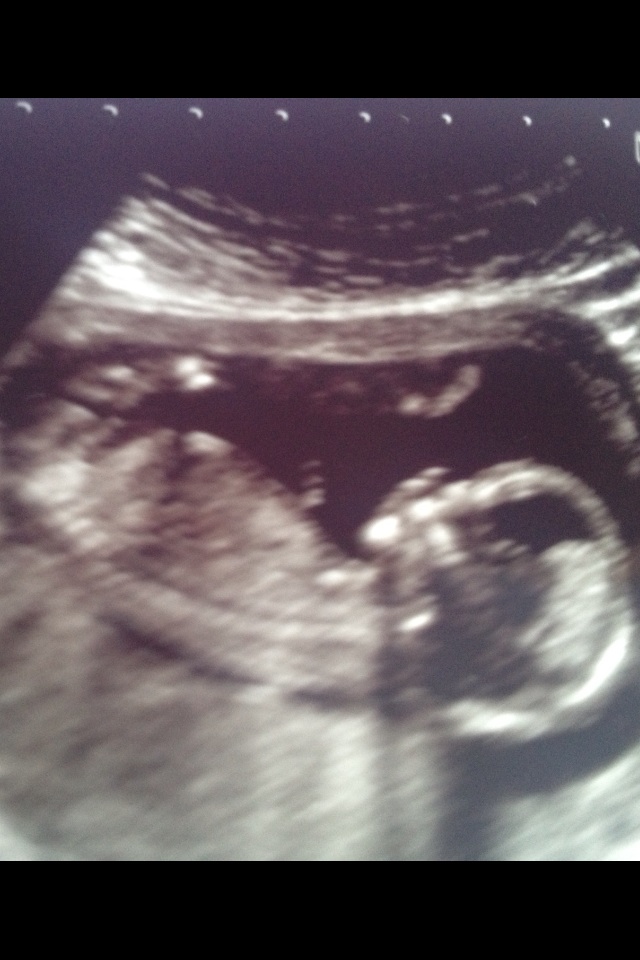

Attachment 9399Attachment 9399 I have 2 weeks until my 20 week scan but any guesses from my pic :D